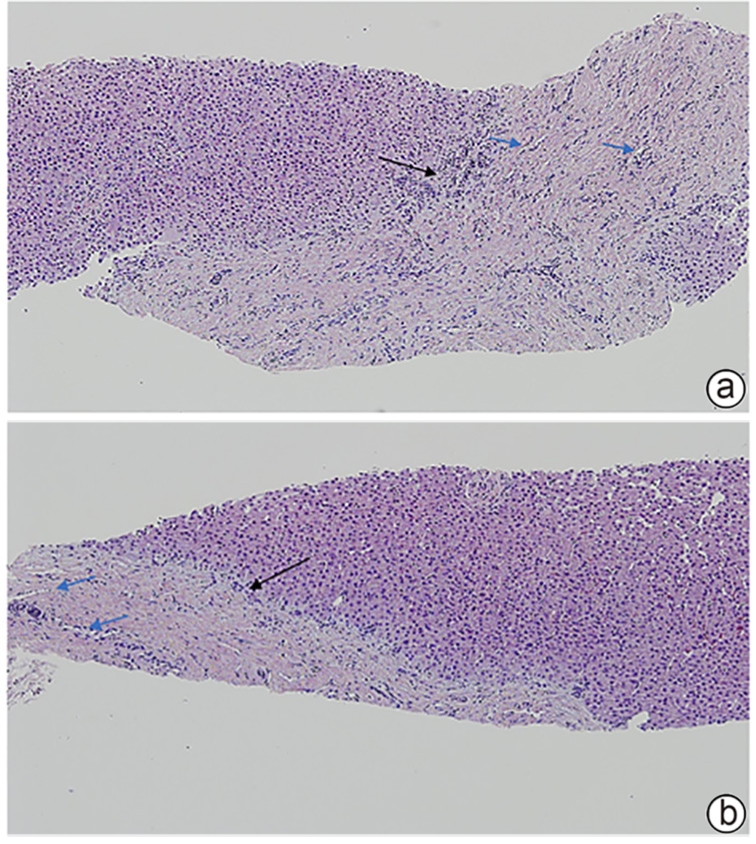

Objectives To summarize the clinical and pathological features of patients with congenital liver fibrosis (CHF), and to investigate the differences in clinical and pathological features between patients in different age groups. Methods A retrospective analysis was performed for the clinicopathological data of 26 patients with pathologically confirmed CHF in China-Japan Friendship Hospital from August 2005 to June 2023, and the patients were stratified by age to investigate the clinical and pathological features of patients in different age groups. Results Among the 26 patients, there were 12 male patients and 14 female patients, with an age of onset of 4 — 61 years. There were 19 patients with portal hypertension type (73.08%), 2 patients with cholangitis type (7.69%), 4 patients with mixed type (15.38%), and 1 patient with occult type (3.85%). Of all 26 patients, 4 had unknown clinical symptoms, and among the 22 patients with clear clinical symptoms, 10 (45.45%) attended the hospital due to upper gastrointestinal bleeding caused by portal hypertension. Pathological manifestations included roughly normal liver parenchyma separated by fibrous septa in the portal area, with the presence of abnormal reactive bile duct hyperplasia. Denser fibrous septa and a lack of portal veins with the corresponding caliber were observed in 4 pediatric patients with disease onset before the age of 10 years, with a significant reduction or even disappearance of compensatory thin-walled blood vessels. Conclusion Portal hypertension-type CHF is the most common type in clinical practice. Patients with an early age of onset have certain histopathological features of the liver, with the presence of serious complications associated with portal hypertension. Therefore, liver biopsy should be performed for patients suspected of CHF in clinical practice, and genetic testing should be performed when necessary. Early identification and diagnosis are of great importance for improving the prognosis of patients.